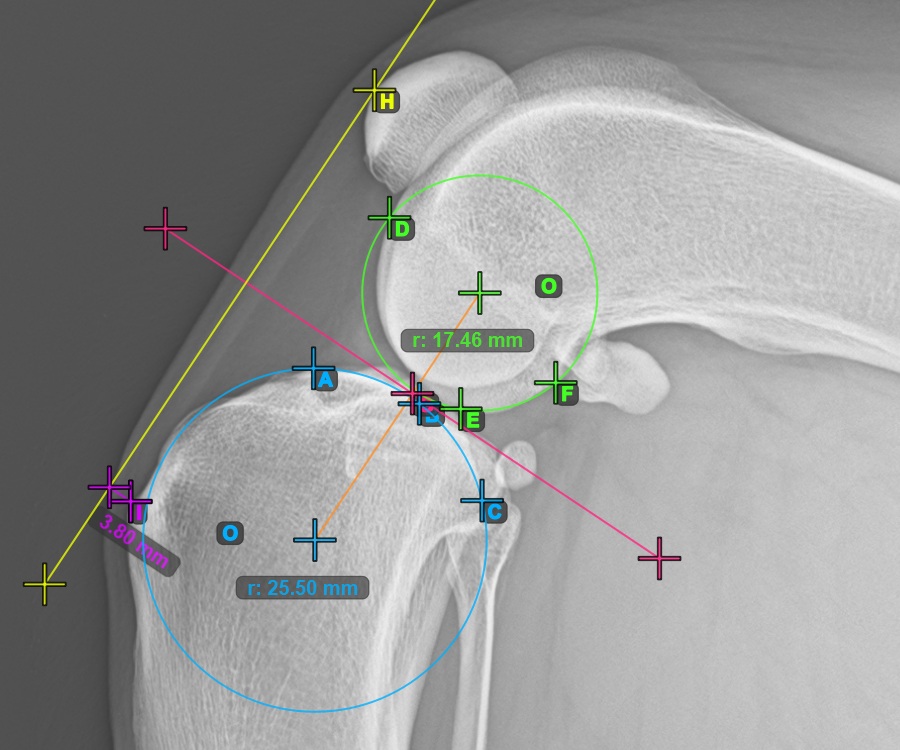

Starten Sie das TTA-Messverfahren, indem Sie den vordersten Punkt der Patella markieren.

Das Bild unten zeigt die übliche Platzierung des vordersten Punkts der Patella.

Um die TTA - 1 Kondylus-Variante des TTA-Messverfahrens abzuschließen, markieren Sie den hintersten Punkt der Crista Tibiae (Tuberositas Tibiae). Der Abstand zwischen der Tuberositas Tibiae und der Linie, die durch den vordersten Punkt der Patella verläuft, ist die erforderliche Anpassung für das TTA-Verfahren.

Das Bild unten zeigt die übliche Platzierung der Tibiatuberositas, des markantesten Punkts des Tibiakamms.